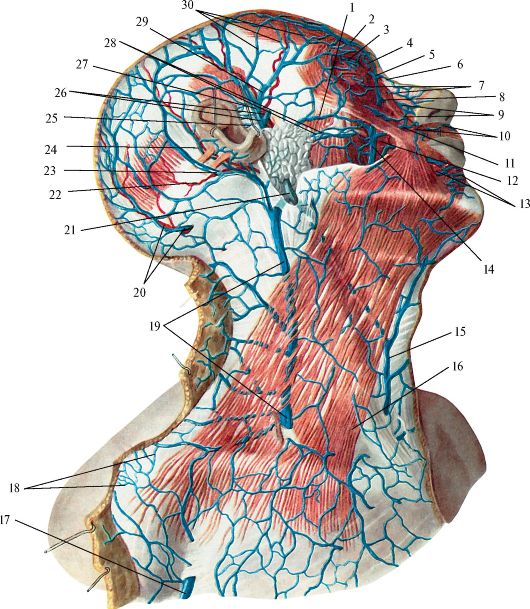

Анатомия внутренней яремной вены: КТ изображения